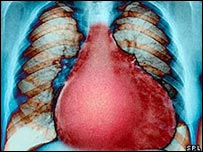

बढ़ा हुआ दिल

मोटे लोगों, उच्च रक्तचाप वालों और डायबिटीज़ के मरीज़ों का दिल अक्सर बढ़ा हुआ होता है

मोटे लोगों, उच्च रक्तचाप वालों और डायबिटीज़ के मरीज़ों का दिल अक्सर बढ़ा हुआ होता है.